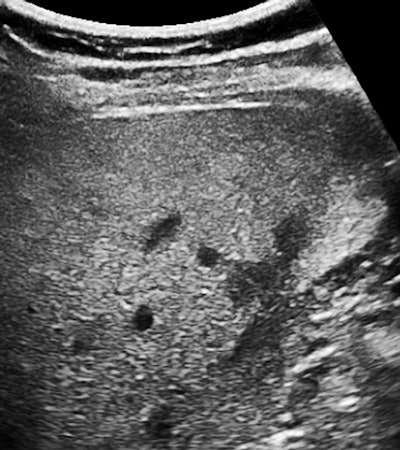

Have a glance at the image below. There is one more related, practical concern for this imaging task. We tend to think of fatty liver as one of the "diffuse" liver diseases, affecting all of the liver uniformly. The first few times you see a rounded, less-reflective "nodule" within a fatty liver, you will assume that this has to be a metastatic lesion, even though the fine detail does not look the way you expect a met to appear.

I can remember doing some ultrasound-guided liver biopsies of such nodules back in the early 1980s. The results always came back "normal liver." Of course we worried that maybe the biopsy missed the lesion, until we learned that these were actually islands of normal liver that had not yet or were somehow resistant to fatty accumulation. The following image has a peripheral zone that has been spared.

Since the 1990s and mainly via CT scans, it has been known that fatty livers can have a geographic pattern with various zones of fatty and normal tissue. I once saw a right lobe that looked like a yin-yang sign with a bright top and a curved border over a normal lower section. The reason I mention this is that when the issue is an SNP, you will have a diffuse pattern when all of the cells are afflicted and something very different when there is a genetic mosaic.